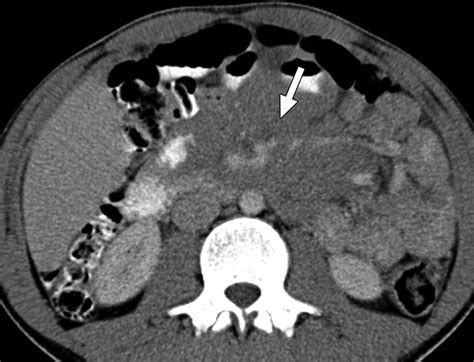

Imaging Scans (CT, PET, MRI) Creating detailed pictures to determine the location and size of tumors.

Bone Marrow Aspiration Checking if cancer cells have spread to the bone marrow.